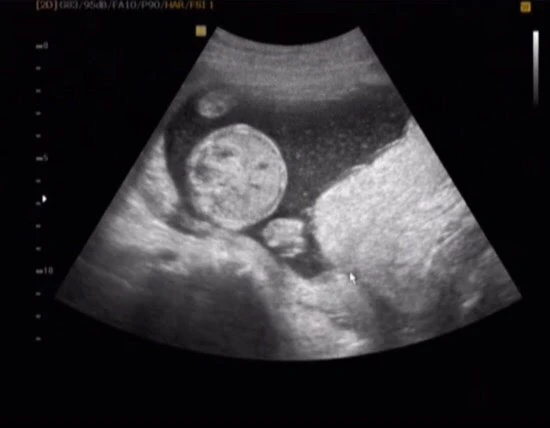

초음파 사진에 조그만 하얀 화살표 있는 곳이 자궁 입구와 태반이 만나는 곳. 태반이 자궁입구에 걸쳐있었다. 반이 자궁을 막는 전치태반 끼가 있다고 하셨다. 폭풍 검색으로 전치태반에 대해 검색했던 내용들. 나는 주수가 일러 뭐라 말할 순 없지만 부분 전치태반인 것으로 보였다. (웃는 게 웃는 게 아님)